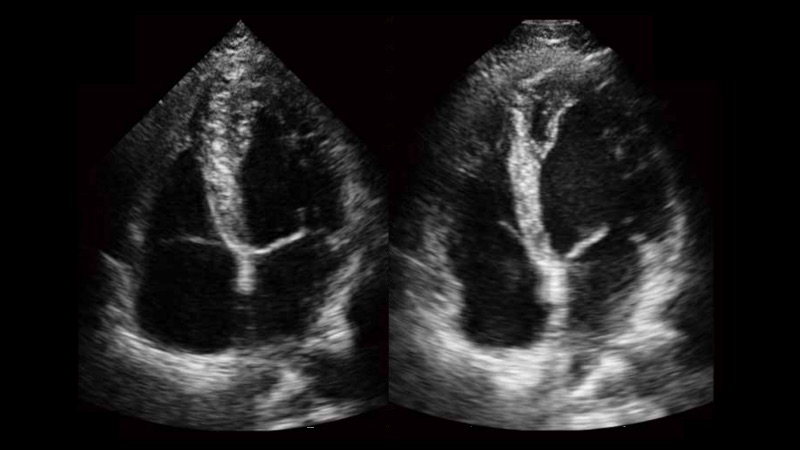

新一代微米成像技术大大提高了器官和病变的可见性。高清对比度分辨率将抑制斑点噪声,同时保持真实的组织结构。